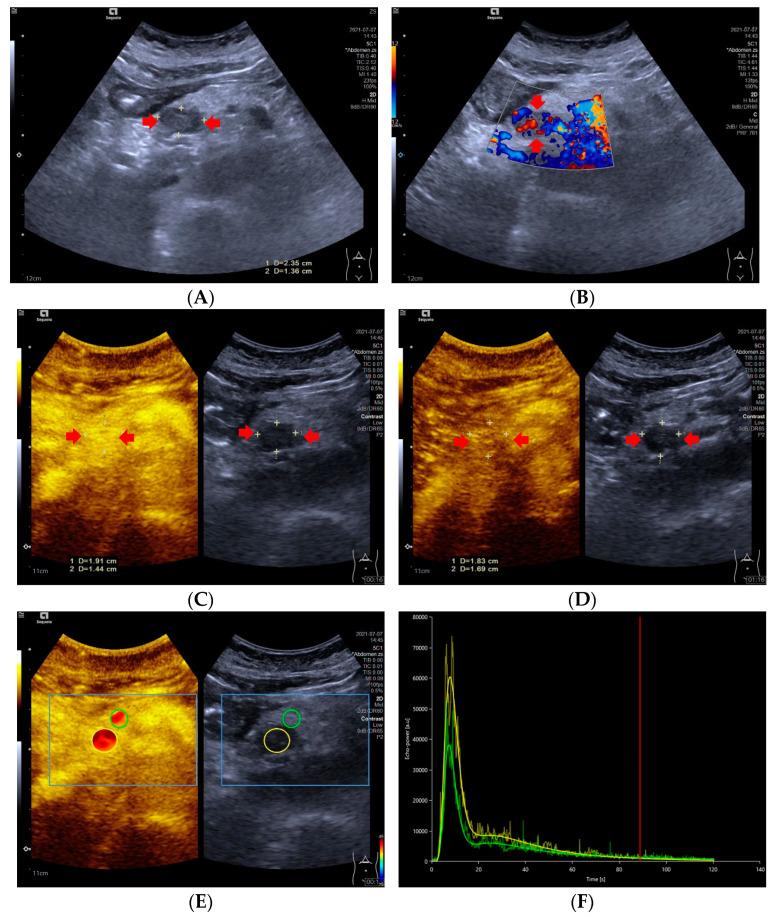

Objective: To investigate whether the dynamic contrast-enhanced ultrasound (DCE-US) analysis and quantitative parameters could be helpful for predicting histopathologic grades of pancreatic neuroendocrine tumors (pNETs). Methods: This retrospective study conducted a comprehensive review of the CEUS database between March 2017 and November 2021 in Zhongshan Hospital, Fudan University. Ultrasound examinations were performed by an ACUSON Sequioa unit equipped with a 3.5 MHz 6C−1 convex array transducer, and an ACUSON OXANA2 unit equipped with a 3.5 MHz 5C−1 convex array transducer. SonoVue® (Bracco Inc., Milan, Italy) was used for all CEUS examinations. Time intensity curves (TICs) and quantitative parameters of DCE-US were created by Vuebox® software (Bracco, Italy). Inclusion criteria were: patients with histopathologically proved pNETs, patients who underwent pancreatic B-mode ultrasounds (BMUS) and CEUS scans one week before surgery or biopsy and had DCE-US imaging documented for more than 2 min, patients with solid or predominantly solid lesions and patients with definite diagnosis of histopathological grades of pNETs. Based on their prognosis, patients were categorized into two groups: pNETs G1/G2 group and pNETs G3/pNECs group. Results: A total of 42 patients who underwent surgery (n = 38) or biopsy (n = 4) and had histopathologically confirmed pNETs were included. According to the WHO 2019 criteria, all pNETs were classified into grade 1 (G1, n = 10), grade 2 (G2, n = 21), or grade 3 (G3)/pancreatic neuroendocrine carcinomas (pNECs) (n = 11), based on the Ki−67 proliferation index and the mitotic activity. The majority of the TICs (27/31) of pNETs G1/G2 were above or equal to those of pancreatic parenchyma in the arterial phase, but most (7/11) pNETs G3/pNECs had TICs below those of pancreatic parenchyma from arterial phase to late phase (p < 0.05). Among all the CEUS quantitative parameters of DCE-US, values of relative rise time (rPE), relative mean transit time (rmTT) and relative area under the curve (rAUC) were significantly higher in pNETs G1/G2 group than those in pNETs G3/pNECs group (p < 0.05). Taking an rPE below 1.09 as the optimal cut-off value, the sensitivity, specificity and accuracy for prediction of pNETs G3/pNECs from G1/G2 were 90.91% [58.70% to 99.80%], 67.64% [48.61% to 83.32%] and 85.78% [74.14% to 97.42%], respectively. Taking rAUC below 0.855 as the optimal cut-off value, the sensitivity, specificity and accuracy for prediction of pNETs G3/pNECs from G1/G2 were 90.91% [66.26% to 99.53%], 83.87% [67.37% to 92.91%] and 94.72% [88.30% to 100.00%], respectively. Conclusions: Dynamic contrast-enhanced ultrasound analysis might be helpful for predicting the pathological grades of pNETs. Among all quantitative parameters, rPE, rmTT and rAUC are potentially useful parameters for predicting G3/pNECs with aggressive behavior.

目的